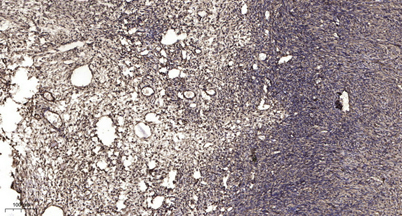

IHC

IHC-p 1:50-300